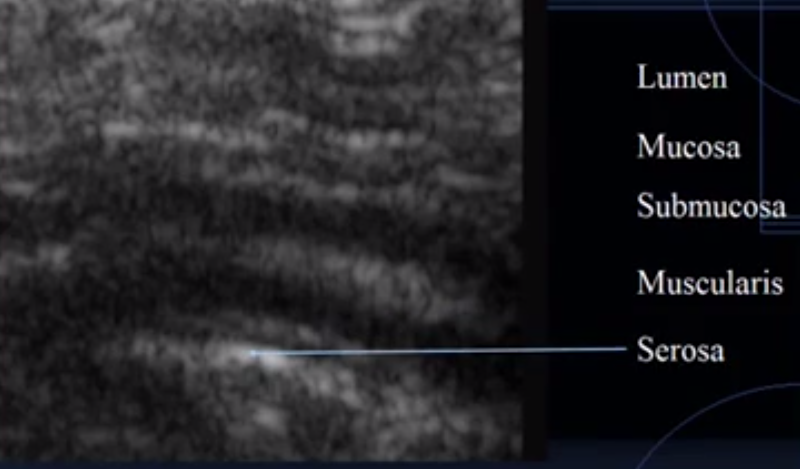

What does this image show?

Intestine

Which is the lumen?

Which is the mucosal layer?

Which is the submucosa layer?

Which is the muscularis layer?

Which is the serosal layer?